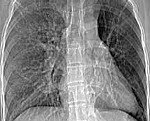

Обстеження рентгеном та КТ

Простіше кажучи, без цих технологій лікарям було б як без рук. Виявлення змін у легенях просто неможливо без допомоги обладнання. Дивовижно, як ми вміємо бачити людину зсередини, чи не так?